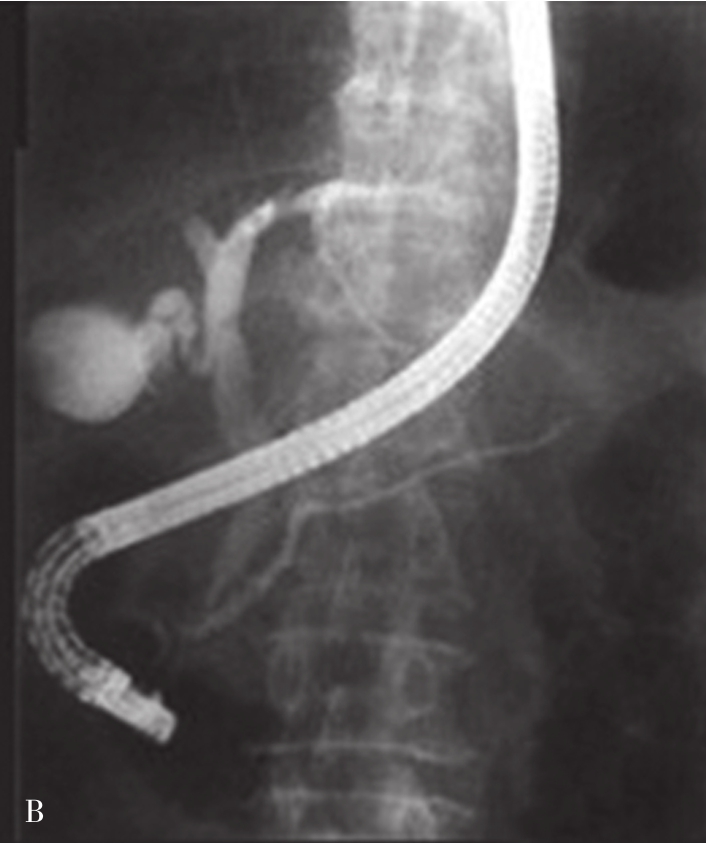

内镜逆行胰胆管造影(endoscopic retrograde cholangiopancreatography,ERCP)指将十二指肠镜插至十二指肠降部,找到十二指肠乳头,由活检管道内插入造影导管至乳头开口部,注入造影剂后进行X线透视和摄片,以显示胰胆管的技术。临床上是显示胰胆管的主要方法之一。它使成像的胆管系统可达到最大可能的范围,若插管成功,注入造影剂,可见内镜逆行胰胆管造影(图5-21-45)。同时可以进行各种治疗程序。如胆总管结石的诊疗中,以往需要外科手术治疗,存在手术创伤大、术后恢复慢、结石残余或复发等难题。在采用ERCP后只需通过十二指肠乳头小切口,即可对肝外胆管结石(图5-21-46)进行碎石、取石、清理等操作。ERCP最早的报道在1968年,随着器械和技术的进步,而在临床上得到推广应用。目前,临床上应用ERCP并不是单纯为了诊断胆管系统的疾病,因为已有了更微创和有效的手段,如磁共振胰胆管成像(magnetic resonance cholangiopancreatography,MRCP)和超声内镜(endoscopic ultrasound,EUS),而主要应用在处理胆道的疾病。适应证主要有胆道梗阻引起的黄疸,如急性胆管炎、胆总管结石、胆道狭窄、胆漏、胆道出血和Oddi括约肌功能紊乱等。内脏穿孔为绝对禁忌证,凝血功能异常、无并发症的急性胰腺炎和心肌梗死都是相对禁忌证。以下简述其技术方法:

图5-21-46 内镜逆行胰胆管造影法示肝外胆管结石

可见胆总管(CBD)内结石(GS)影像(直径大于2cm)